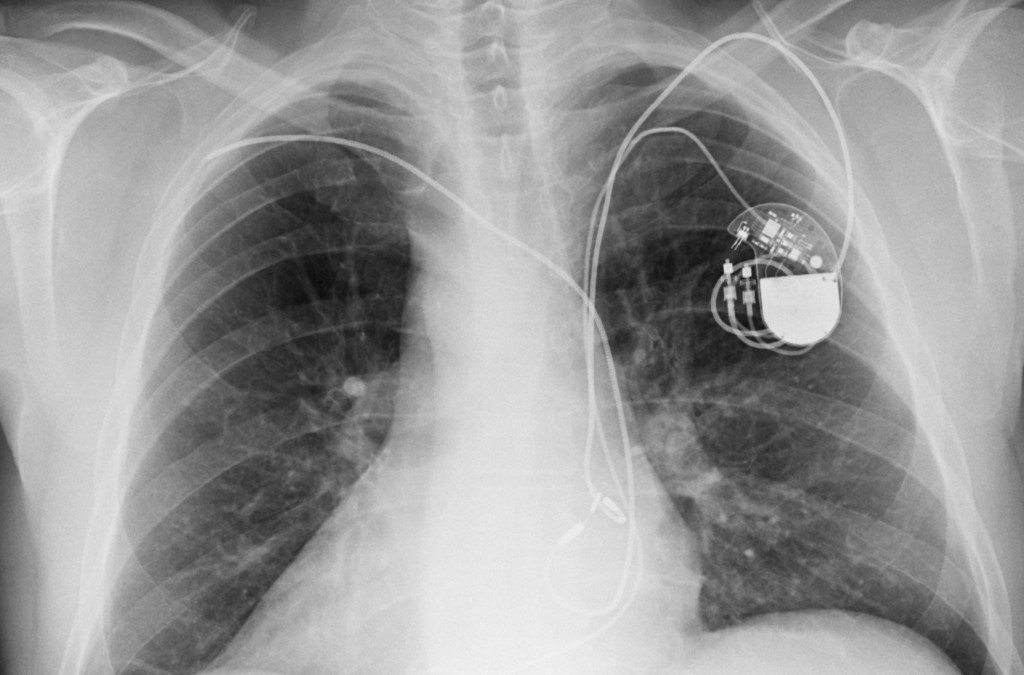

These small cardio-defibrillators are implanted in a patient’s chest to deliver small electrical shocks to prevent irregular or dangerously fast heartbeats, which can prove fatal. Most modern devices come with wireless or radio-based technology to allow patients to monitor their conditions and their doctors to adjust settings without having to carry out an invasive surgery.

More than 20 different Medtronic defibrillators and models are affected, the alert said, including the CareLink programmer used in doctor’s offices and the MyCareLink monitor used in patient homes.